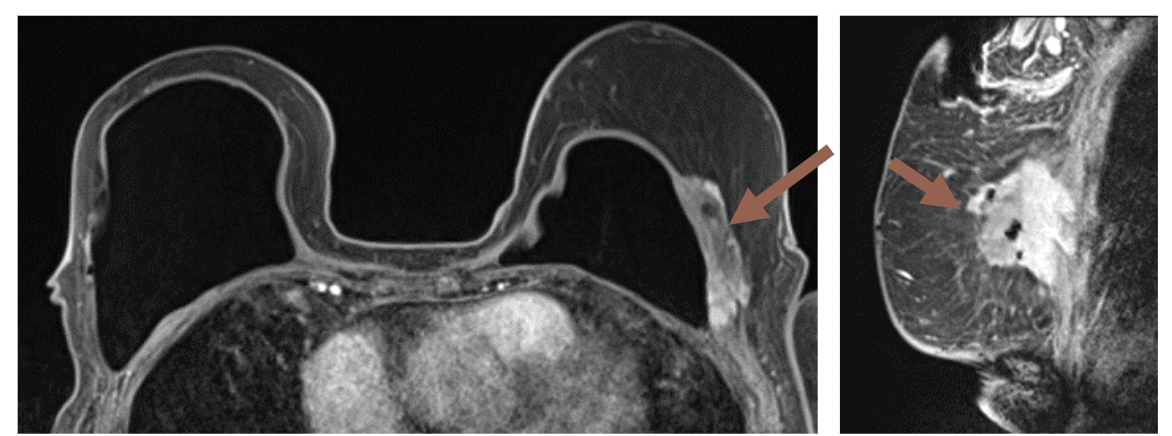

5. Редкая и местно-агрессивная фибробластная десмоидная опухоль может имитировать рак молочной железы при маммографическом исследовании с некальцифицированными образованиями неправильной формы с высокой плотностью и спикулированными краями, согласно авторам плаката. Обычно десмоидные опухоли не проявляют потенциала отдаленного метастазирования, при ультразвуковом исследовании они выглядят как гипоэхогенные образования с нечеткими границами, с задним затуханием и толстым эхогенным ободком. Авторы исследования добавили, что МРТ-изображения с Т1-взвешенным изображением будут показывать нечеткие гипо- и изоинтенсивные образования, тогда как Т2-взвешенные изображения выявляют неоднородные гиперинтенсивные образования.

«(Десмоидные опухоли) демонстрируют подозрительное медленное улучшение после введения контраста», — отметили Шах и его коллеги. «(МРТ) также полезно показать вовлечение грудной клетки».